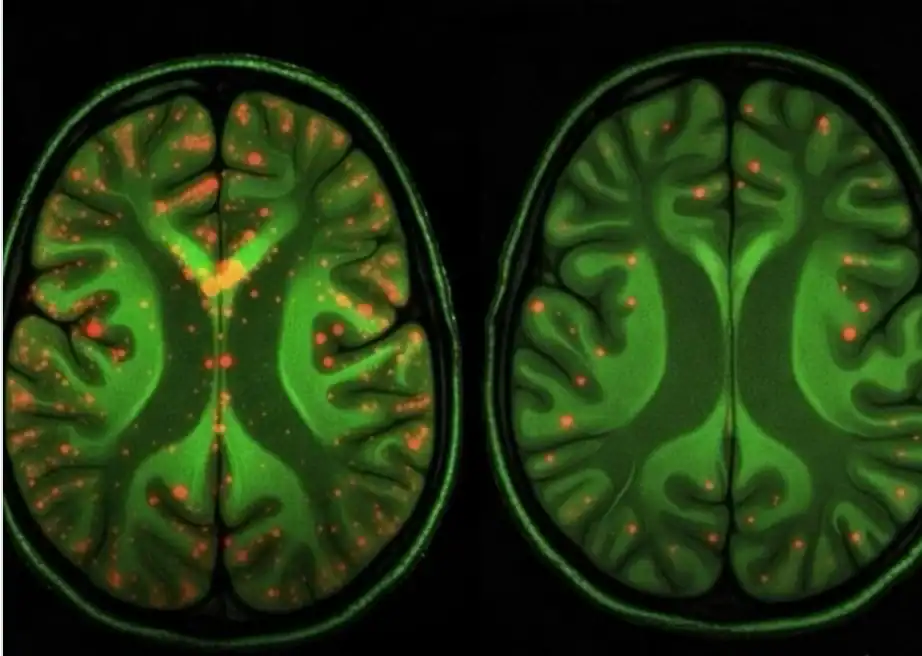

Pesquisadores anunciaram um avanço considerado promissor no combate ao Doença de Alzheimer. Estudos experimentais conseguiram remover placas beta-amiloides do cérebro, estruturas tóxicas associadas à progressão da doença.

Essas placas se acumulam entre os neurônios e prejudicam a comunicação entre as células cerebrais. O processo está relacionado a sintomas como perda de memória, confusão mental e declínio cognitivo.

Nos experimentos, cientistas observaram que a remoção dessas estruturas levou a melhora em sinais neurológicos e a uma recuperação parcial da atividade cerebral nos modelos analisados.

O tratamento utiliza tecnologias de biotecnologia associadas a anticorpos específicos. Essas moléculas são projetadas para reconhecer as placas beta-amiloides e eliminá-las sem causar danos aos neurônios saudáveis.